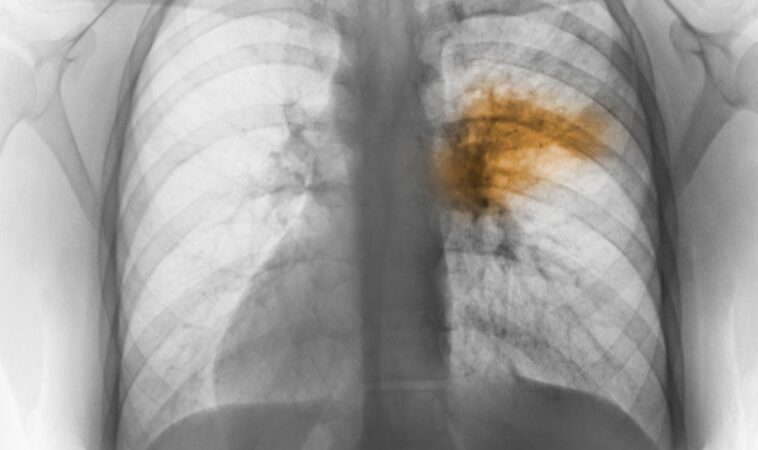

- Ακτινογραφία θώρακα: εντοπίζει τη φλεγμονή